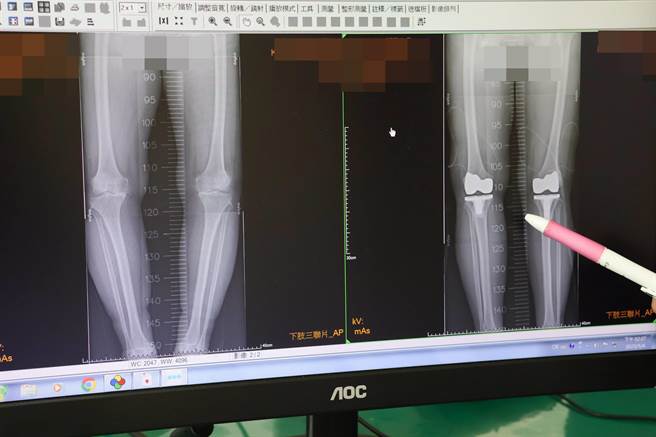

患者術前(左)膝蓋嚴重變形無法走路,術後(右)已恢復正常。(大甲李綜合醫院提供)